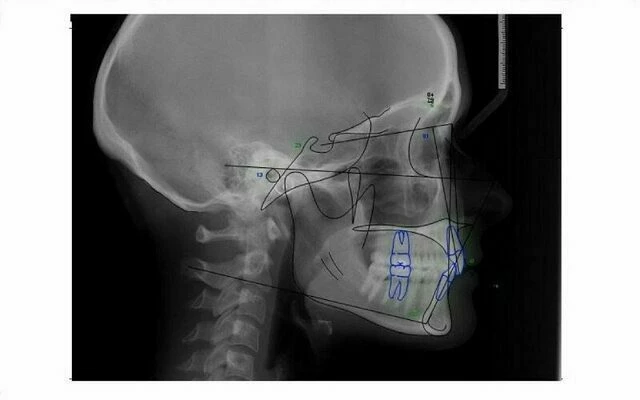

Kỹ thuật Tracing và Phân tích Phim Cephalometric

Kỹ thuật tracing phim Cephalometric là một bước quan trọng trong phân tích phim Cephalometric, đòi hỏi sự tỉ mỉ và hệ thống. Đầu tiên, nên kiểm tra tổng thể Cephalogram, sau đó xác định và định vị các điểm mốc giải phẫu trên Cephalogram. Tiếp theo là tìm các cấu trúc giải phẫu sọ mặt theo một trình tự hợp lý, và cuối cùng là xây dựng các điểm mốc và các đường thẳng cần thiết cho việc đo đạt sọ mặt bằng Cephalometric.

Các bước thực hiện Kỹ thuật Tracing

Để thực hiện kỹ thuật tracing phim Cephalometric một cách chính xác, các bước sau đây cần được tuân thủ:

- Vẽ ít nhất hai dấu cộng chữ thập ở góc bên phải và trái của phim. Chúng không trùng với bất kỳ điểm mốc giải phẫu nào và được dùng để định hướng khi tracing trên phim.

- Tìm đường chỉ nét mặt nhìn nghiêng của mô mềm sọ mặt, bờ ngoài sọ và đốt sống cổ.

- Tìm nền sọ, bờ trong xương sọ, xoang trán và thanh thai. (Moorrees kiến nghị nên bỏ vị trí porion và thay bằng bờ trên của chỏm lồi cầu để xác định Mặt phẳng Frankfort).

- Tiếp theo, tìm xương hàm trên và các cấu trúc liên quan bao gồm các gờ chính (tiêu biểu là mỏm xương gò má) và rãnh chân bướm – hàm trên. Sàn mũi cũng được vẽ dọc theo gai mũi trước và gai mũi sau. Răng cối lớn thứ nhất hàm trên và răng cửa hàm trên nằm trước nhất (gồm cả chân răng của nó) cũng được vẽ ra.

- Cuối cùng là xương hàm dưới, bao gồm vị trí ráp nối giữa, bờ dưới xương, lồi cầu và mõm vẹt. Răng cối lớn thứ nhất hàm dưới và răng cửa nằm phía trước nhất bao gồm cả chân răng cũng được vẽ ra. Ống thần kinh răng dưới cũng có thể được vẽ và đôi khi có thể dùng nó để làm vị trí chồng phim cho các phim kế tiếp.